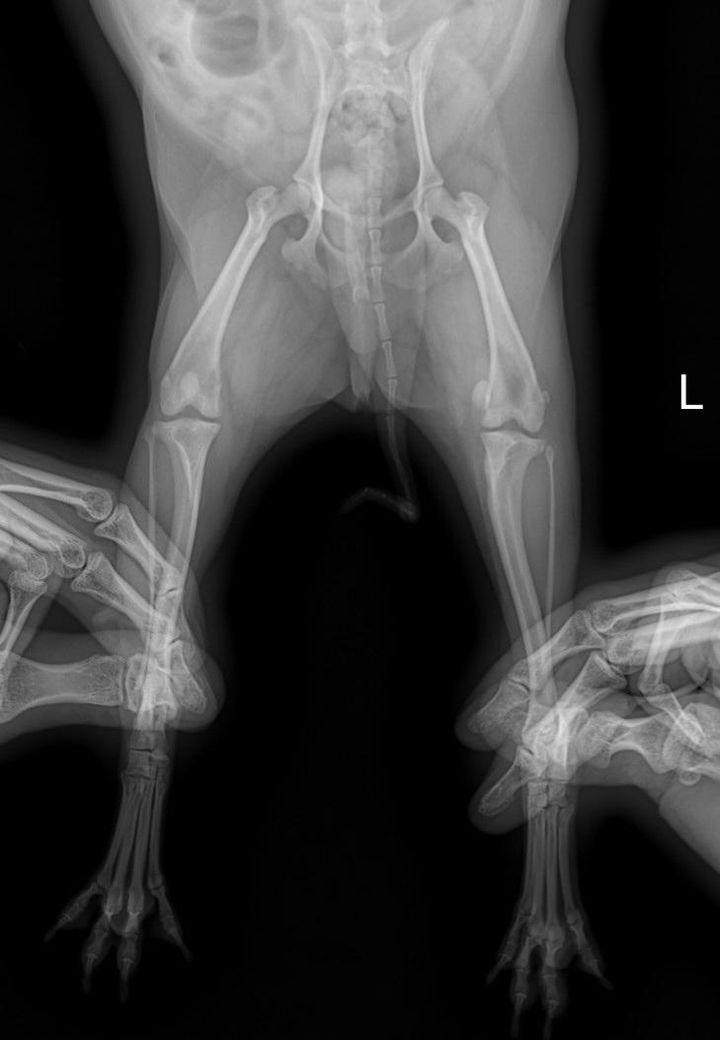

미니포메2살 슬개골 엑스레이 봐주세요

미니포메 2살 강아지

다리가 좀 불편한듯해서 검진받았어요

슬개골수술 해야한다고하던데